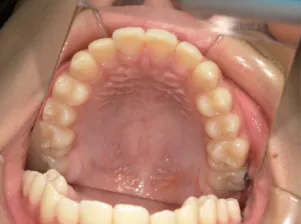

治療後⑩高2:17y7m 抜歯治療終了

| 行ったご提案・診断内容 | 成長期に行う治療と咬合治療をご提案 咬合治療でOPEにならないように、成長期に受け口の悪化予防を行い、咬合治療で歯並びと口元の改善を行うことを提案しました。 《成長期治療:成長時期にお口の環境を整え、適正な成長を誘導する治療》 使用装置 《咬合治療:成長期治療後に大人の歯を咬ませる治療》 *治療は上記ステップで行いました。 《治療後の経過観察》 |